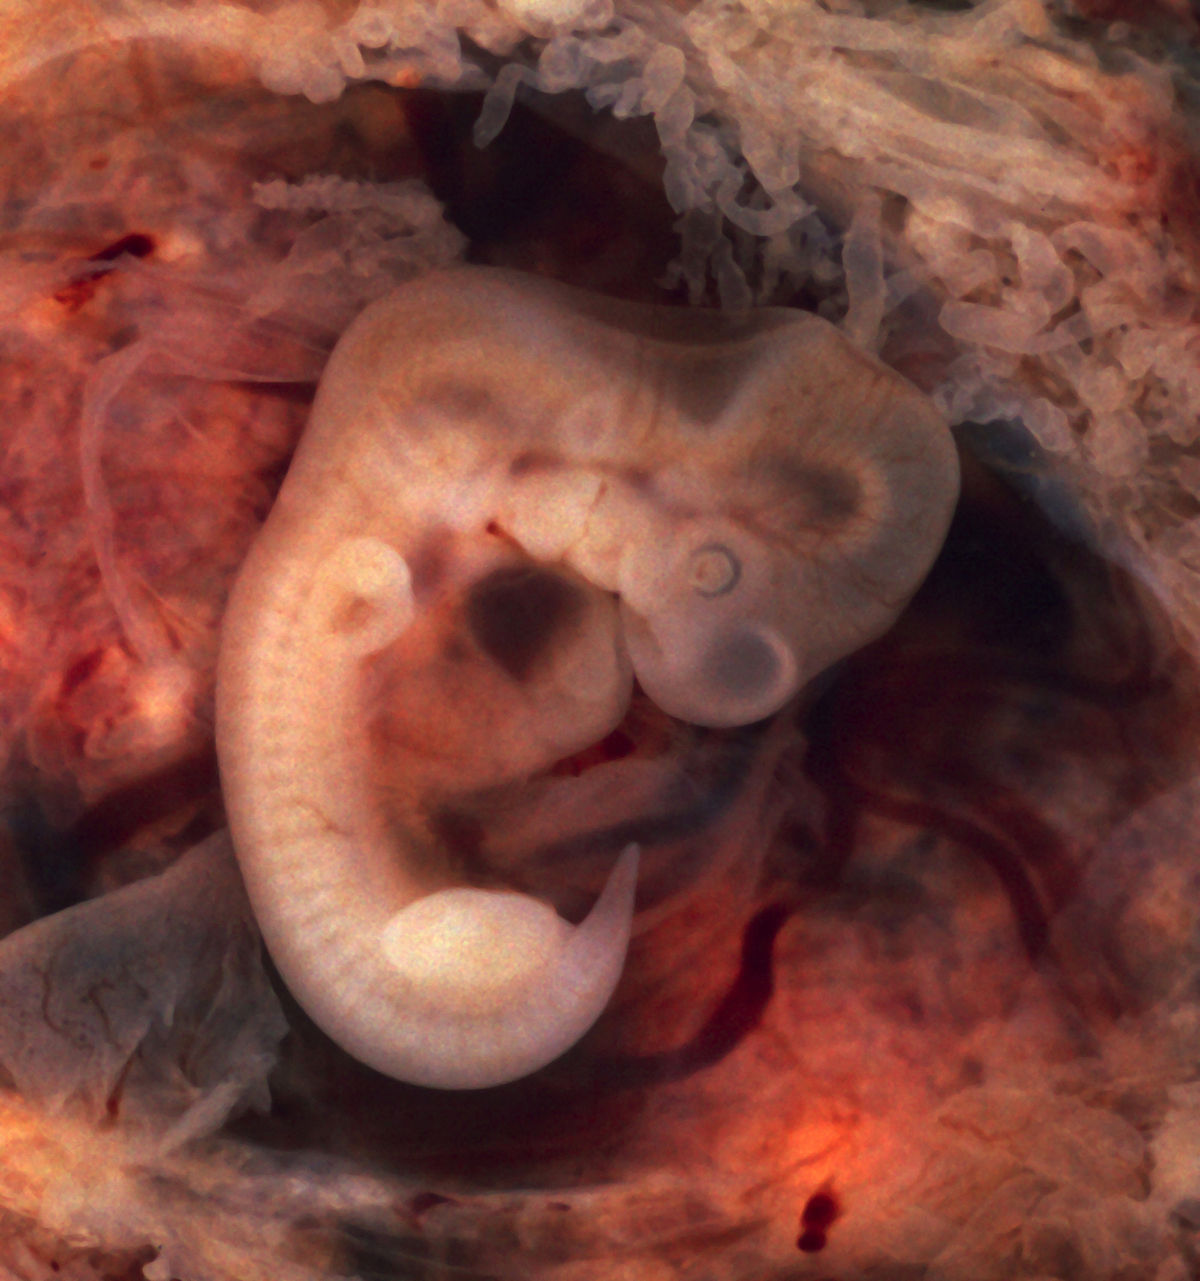

Эмбриональный период: Развитие эмбриона от зачатия до рождения

Раздел: Картинки на заметку